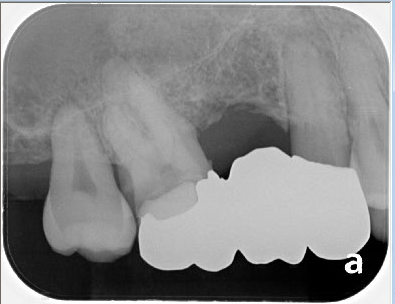

根の中の細菌感染がひどかったためラバーダムで唾液の侵入を防ぎ、無菌的な環境で根管治療を行いました。

レントゲン上で左から2番目と3番目の歯の根管治療をしました。